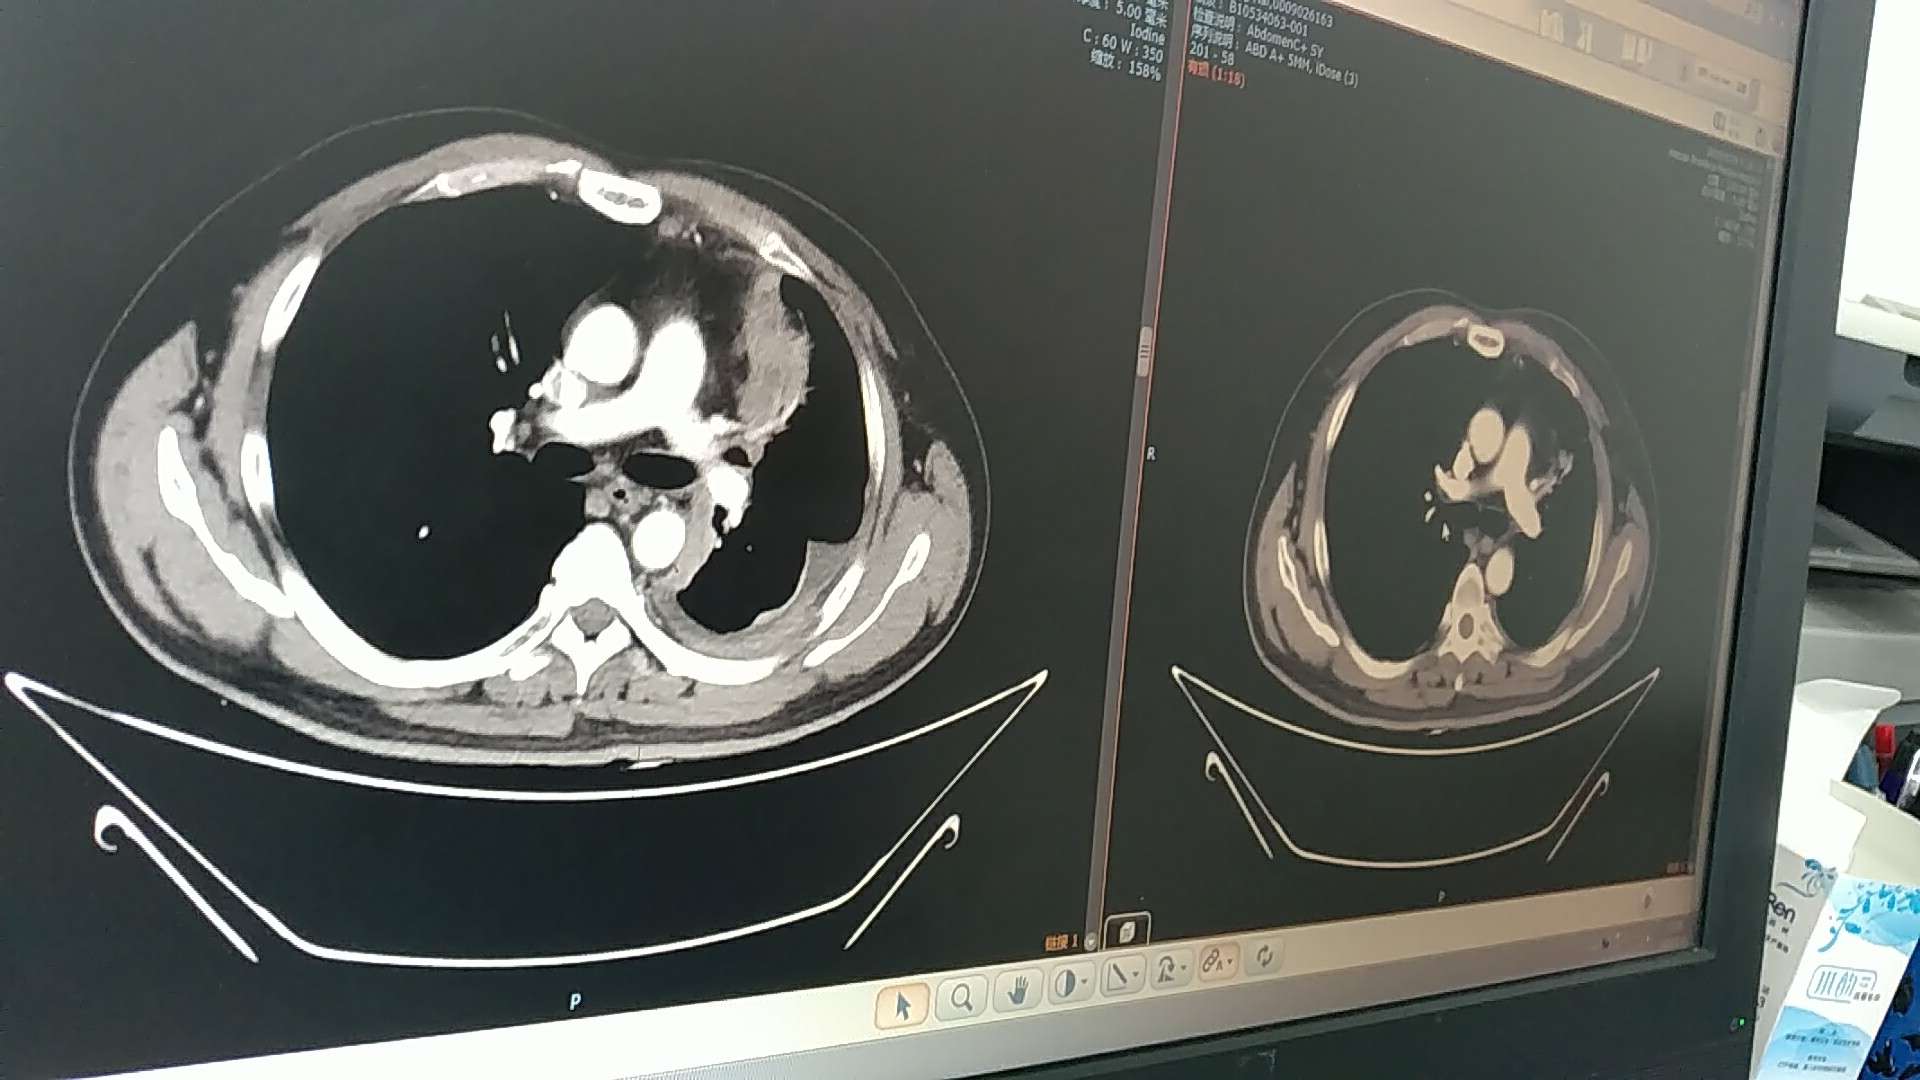

(以下两张照片左为七月,右为八月)

看图片是明显好转了。